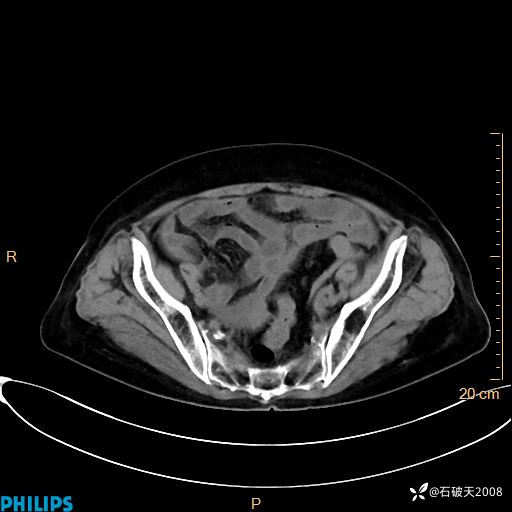

动脉期